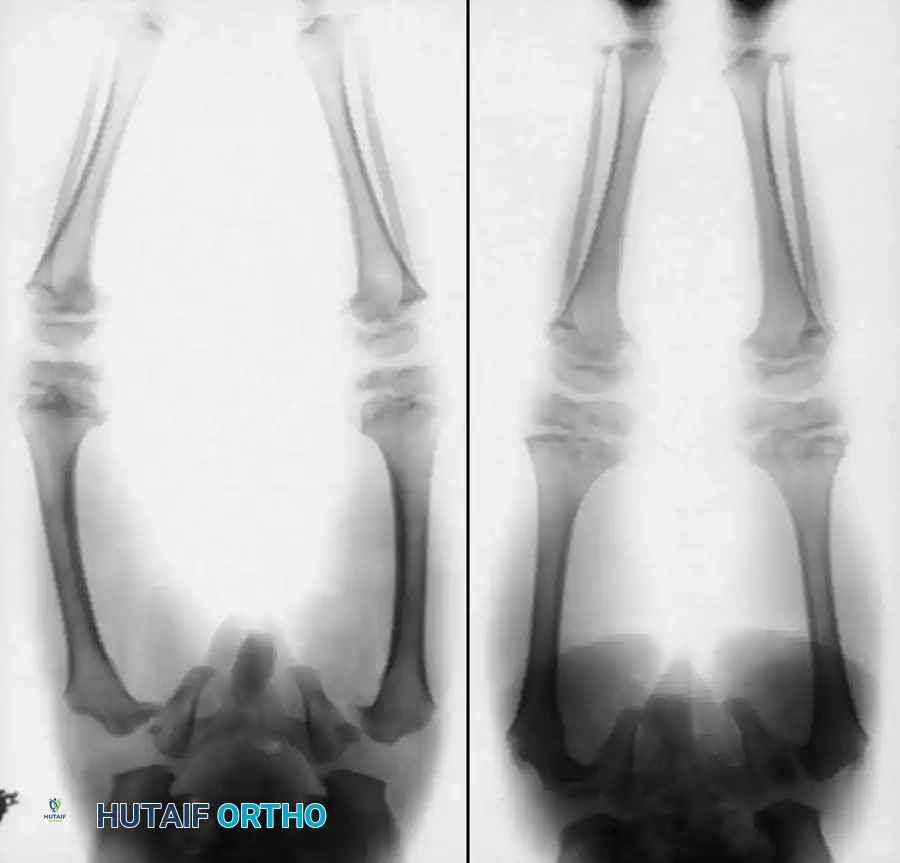

Image

Fig. 29-56: Medullary rod positioning in osteotomies for osteogenesis imperfecta. (A) Incomplete reduction with poor position of the rod; it is not centrally placed and is anterior in the epiphysis. (B) Complete reduction of end fragments and excellent central positioning of the medullary rod.